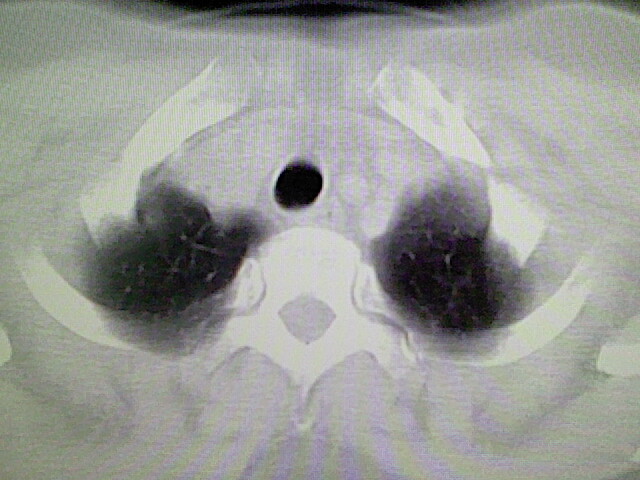

女,52岁,咳嗽,咳痰多日

左下肺陈旧纤维索条!

左肺舌段炎性改变

我见过几例,为炎症后纤维条索

慢性炎症后改变

考虑慢性炎性病灶粘连牵拉改变。

左肺舌叶纤维锁条病变。

左肺上叶下舌段炎症并局部胸膜反应。

左肺舌叶纤维索条影。

左肺舌叶段陈旧性病变

左肺舌段炎性反应。片子的质量太不好了。

左肺舌段炎性

炎性改变

左肺舌叶纤维索条影